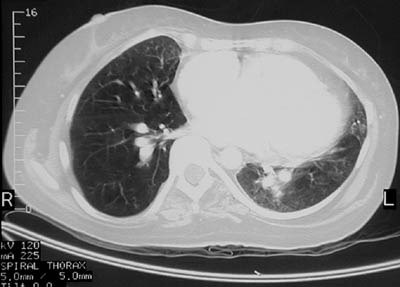

| The chest CT scan above in bone window reveals a discontinuity involving the superior aspect of the interventricular septum. This is consistent with a venticular septal defect that explains the cardiomegaly, particularly of the right ventricle, as seen below in lung window. Over the years, the left-to-right shunt induces increasing pulmonary hypertension, seen as prominent bright pulmonary arteries in the lowest frame below, and the shunt reverses, a so-called Eisenmenger complex. |